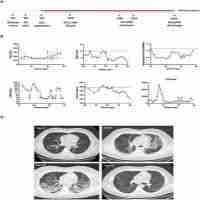

| Abstract | Here we report a critically ill patient who was cured of SARS-CoV-2 infection in Changsha, China. A 66-year-old Chinese woman, with no significant past medical history, developed severe pneumonia-like symptoms and later diagnosed as severe COVID-19 pneumonia. Within two months of hospitalization, the patient deteriorated to ARDS including pulmonary edema and SIRS with septic shock. When treatment schemes such as antibiotics plus corticosteroids showed diminished therapeutic value, hUCMSCs therapy was compassionately prescribed under the patient’s consent of participation. After treatment, there were significant improvement in disease inflammation-related indicators such as IL-4, IL-6 and IL-10. Eventually, it confirmed the therapeutic value that hUCMSCs could dampen the cytokine storm in the critically ill COVID-19 patient and modulated the NK cells. In the continued hUCMSCs treatment, gratifying results were achieved in the follow-up of the patient. The data we acquired anticipates a significant therapeutic value of MSCs treatment in severe and critically ill patients with COVID-19, while further studies are needed. |